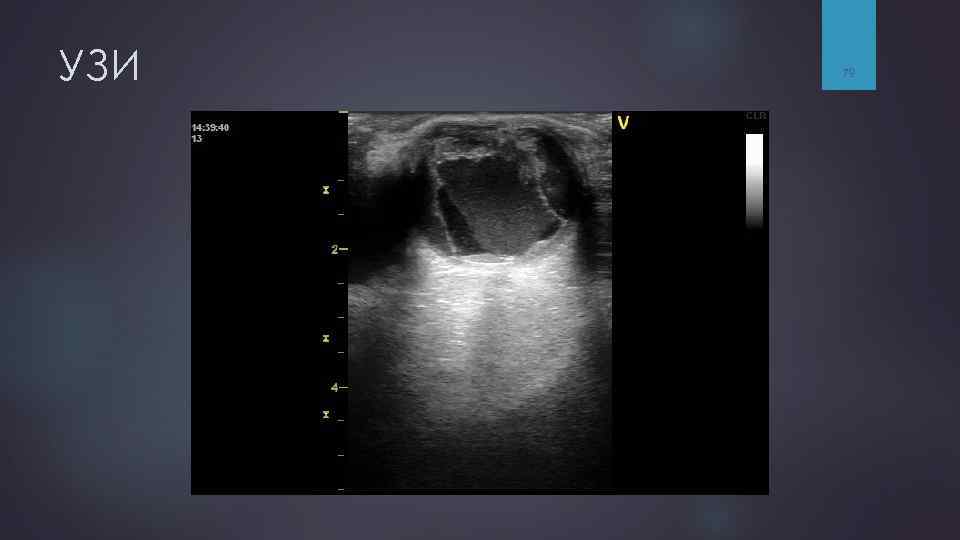

Ультразвуковое исследование (УЗИ) УЗИ применяется для диагностики: сочетанных повреждений лицевого скелета и структур орбиты, § §позволяет §а выявить гемофтальм, отслойку сетчатки, также оценить эти состояния в динамике. Ограничением метода является невозможность оптимально оценить состояние костных структур. 77

УЗИ 78

УЗИ 79